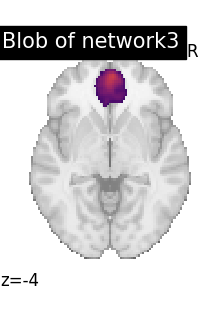

# To reduce the complexity, we choose to display all the regions

# extracted from network 3

import numpy as np

DMN_network = index_img(atlas_networks, 3)

regions_indices_network3 = np.where(np.array(extraction.index_) == 3)

for index in regions_indices_network3[0]:

cur_img = index_img(extraction.regions_img_, index)

coords = find_xyz_cut_coords(cur_img)

plotting.plot_stat_map(

cur_img,

display_mode="z",

cut_coords=coords[2:3],

title="Blob of network3",

colorbar=False,

cmap="inferno",

vmax=15,

)